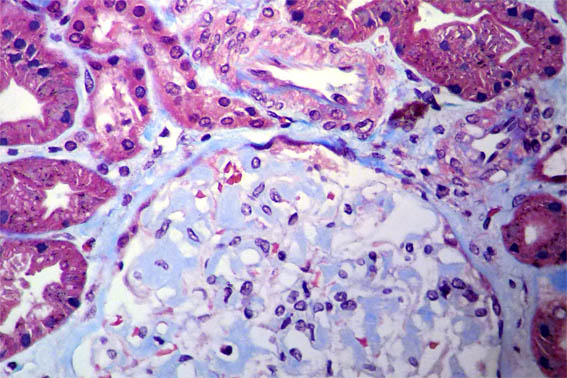

Figure 3.

Masson's

trichrome stain,

X400.